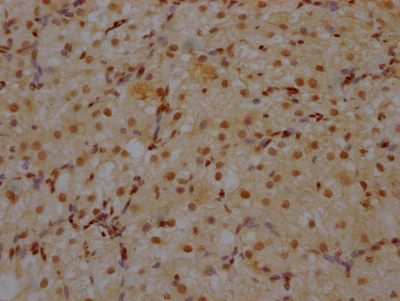

IHC image of CSB-RA930964A0HU diluted at 1:100 and staining in paraffin-embedded human brain tissue performed on a Leica BondTM system. After dewaxing and hydration, antigen retrieval was mediated by high pressure in a citrate buffer (pH 6.0). Section was blocked with 10% normal goat serum 30min at RT. Then primary antibody (1% BSA) was incubated at 4℃ overnight. The primary is detected by a Goat anti-rabbit IgG polymer labeled by HRP and visualized using 0.05% DAB.